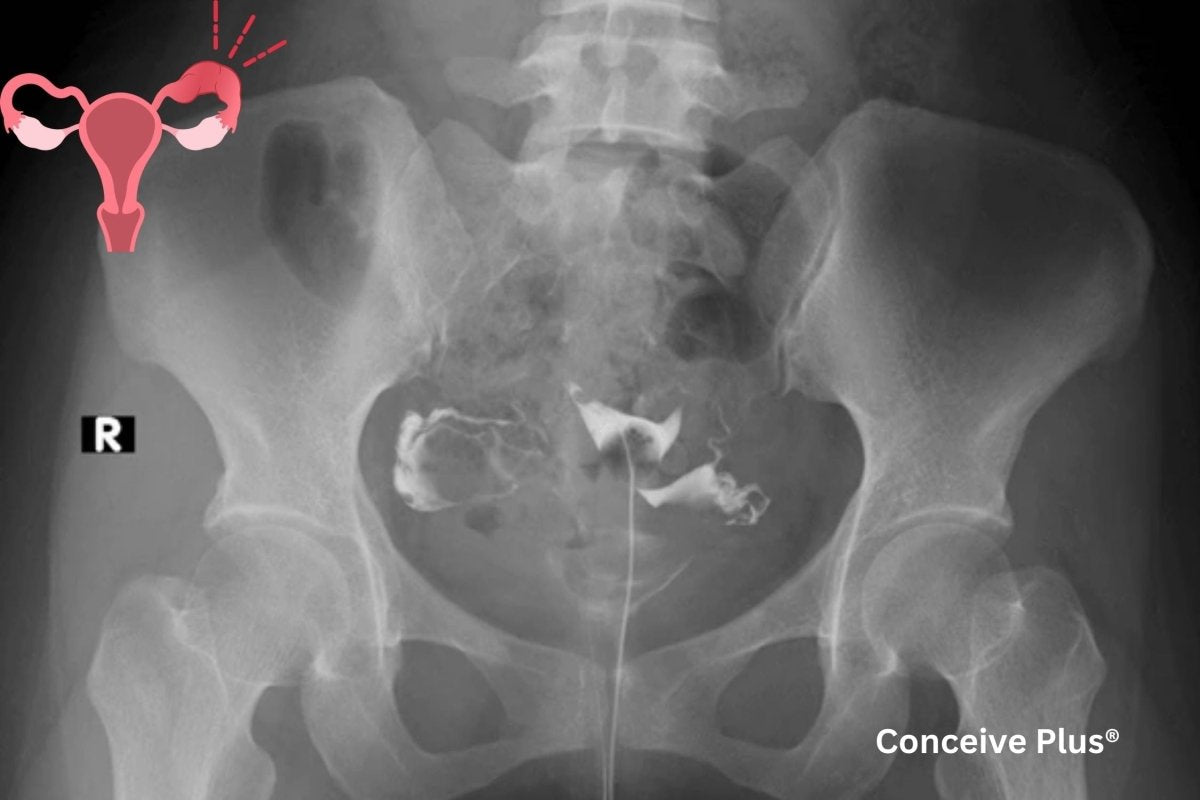

L'hystérosalpingographie consiste à injecter un produit de contraste par le col de l'utérus, ce qui permet aux professionnels de santé de prendre des radiographies de l'utérus et des trompes de Fallope. En évaluant la circulation du produit dans l'appareil reproducteur, les spécialistes peuvent identifier d'éventuels blocages ou problèmes structurels. Cet examen est généralement recommandé aux personnes ayant des difficultés à concevoir ou lorsqu'un professionnel de santé suspecte que la forme ou l'état de l'utérus et des trompes de Fallope puisse jouer un rôle dans les troubles de la fertilité.

L'HSG offrant des informations détaillées, elle est souvent considérée comme l'une des premières étapes des évaluations de fertilité. Réalisée correctement, elle peut fournir des informations cruciales sur les fibromes utérins, les polypes, les tissus cicatriciels ou l'obstruction des trompes de Fallope. Bien que l'intervention elle-même ne dure généralement que quelques minutes, la préparation et le suivi peuvent prolonger la durée totale du séjour en établissement de santé [ 1 ] .